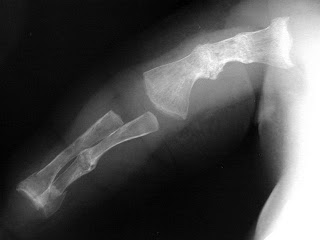

What is your diagnosis?

b) Osteogenesis Imperfecta Type II

b. Osteogenesis Imperfecta Type II